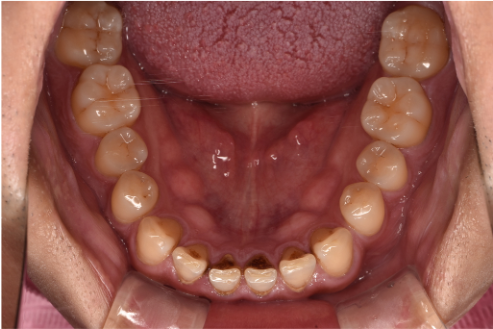

| カウンセリング・診断結果 | こちらの患者様は1日20本ほどタバコを吸われる方で、歯医者は十数年振りとのことでした。 縁上歯石と全体的に縁下歯石が付着しており、歯ぐきが赤く腫れ炎症しておりました。前歯の歯頸部や裏側に着色も認められました。歯周病検査により中等度の歯周炎が認められたため歯周治療も必要でした。 |

| 行ったご提案・治療内容 | 初診時はブラッシング方法などセルフケアについて説明を行い、縁上歯石・着色の除去を行いましました。 歯肉の炎症がある程度落ち着いたところで、後日再評価を行い歯周治療へ移行しました。 |